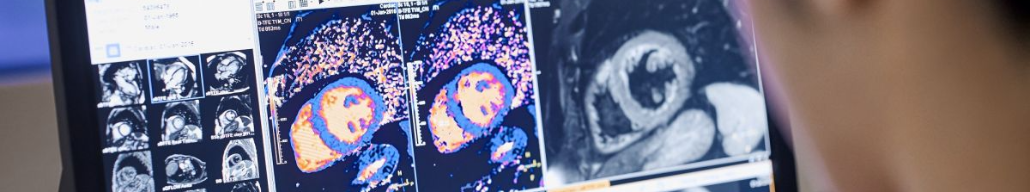

Фото из открытого источника (Яндекс-картинки)